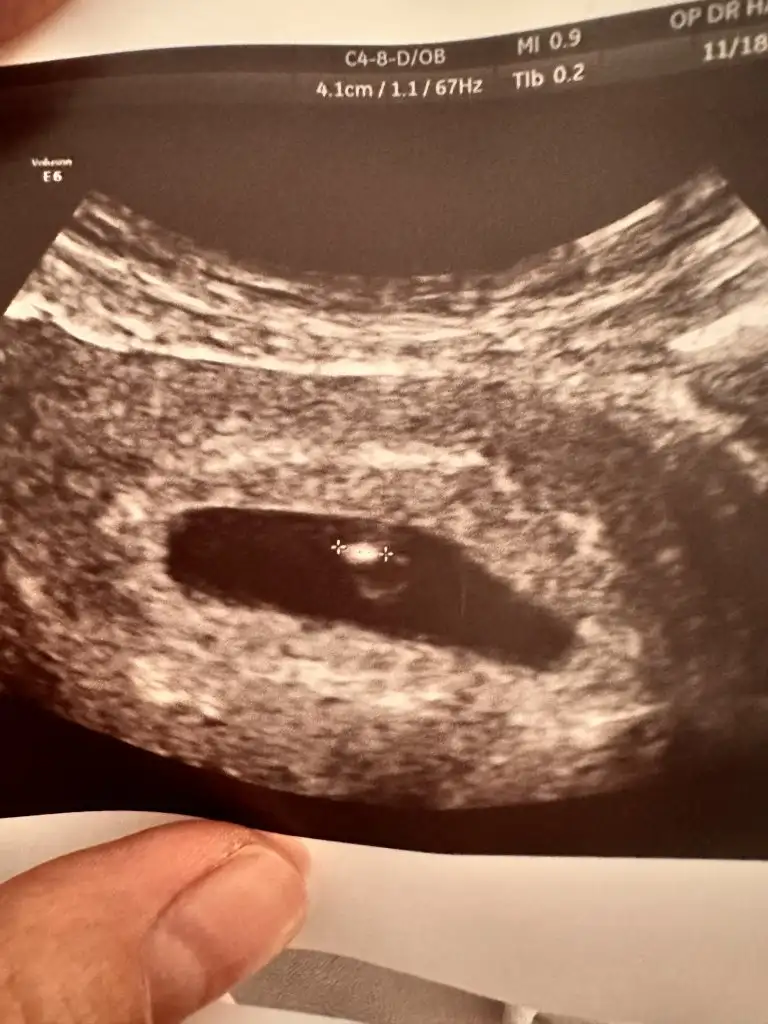

Banada bakabilirminiz 13 haftalık

• IMG_20241117_072114.webp

IMG_20241117_072114.webp

20,7 KB · Görüntüleme: 50